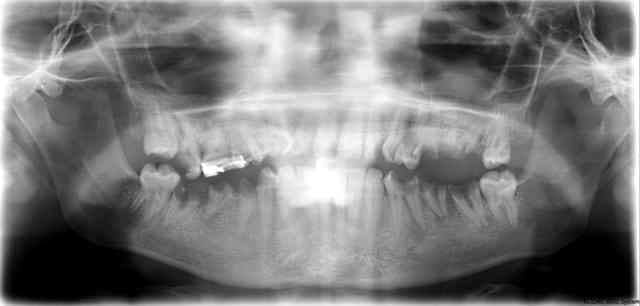

Jeune maman de 21 ans vue en urgence (36) terrorisée!

a part son....truc, en haut a droite, elle n'a jamais eu aucun soins en bouche?

Le truc: un reste de traitement d'ortho.